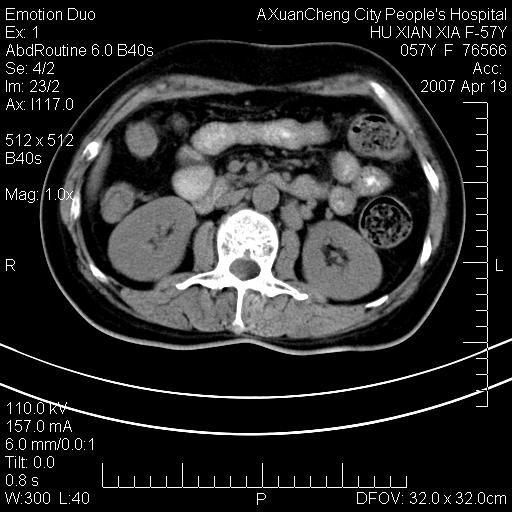

标题: CT7778:[原创]F,57Y腹痛待查,胸片提示肺部占位,应当很典型 [打印本页]

标题: CT7778:[原创]F,57Y腹痛待查,胸片提示肺部占位,应当很典型

胸片提示肺部占位

考虑:1、双侧肾上腺占位.2、肝左叶内侧段不规则低密度灶,建议强化扫描.

忽略了,只以为急腹症,应该支持肺癌肾上腺转移,肺癌患者20-30%发生肾上腺转移

双侧肾上腺增大,有分叶,密度均匀,考虑转移建议查原发灶

1.双侧肾上腺占位,转移首先考虑。

2.肝硬化,门静脉高压;肝左叶内侧段病灶建议增强。

3.12指肠水平段狭窄,建议行低张12指肠造影。

双侧肾上腺结节样肿块,结合肺部肿块,考虑肺癌肾上腺转移。

双侧肾上腺及腹膜后淋巴结增大,结合胸片提示肺部占位,考虑肺癌双侧肾上腺及腹膜后淋巴结转移.